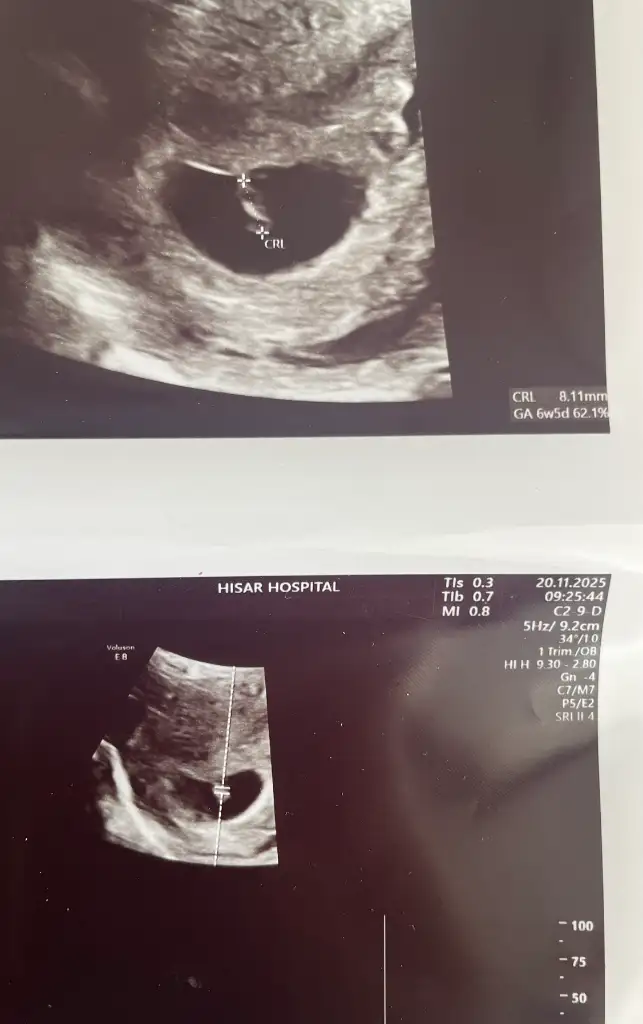

Kızlar doktor seçimi ne kadar önemliymiş bugün anladım. 6+5’teyim bugün. İlk doktorum yeterince açıklayıcı konuşmuyordu. Kalp atışını ilk duyduğumuzda eşimi çağırmak istediğimde “Artık çok duyacak zaten boşver” diye tepki vermişti. Bugün çevremde çok önerilen bir doktora gittim her şeyi tek tek gösterdi anlattı. Ölçüm yaptı, haftasıyla eş gittiğini söyledi. Yeme-içme konusunda da her ayrıntıyı anlattı. İçim o kadar rahat etti ki. Doktorunuz konusunda içiniz rahat etmiyorsa hemen değiştirin ❤🥰

Kızlarrr 6+5den selamlar. Bugün bizde kalp atışını duyduk çok şükür 🙏 rutin kan testlerimi verdim. Bir sonraki doktor randevusu için 11. Haftada çağırdı, fetal dna yaptıracağım. artık 4 hafta 4 ay gibi geçer 😅